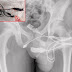

| Apenas as extremidades do cabo USB ficaram para fora do pêni |

Raios-X revelaram que havia um nó no cabo USB dentro do adolescente, o que exigiu que os cirurgiões fizessem uma incisão na região entre o órgão genital e o ânus para arrancá-lo. Eles puxaram as extremidades pela abertura da uretra e cortaram o restante do fio antes de remover os pedaços.